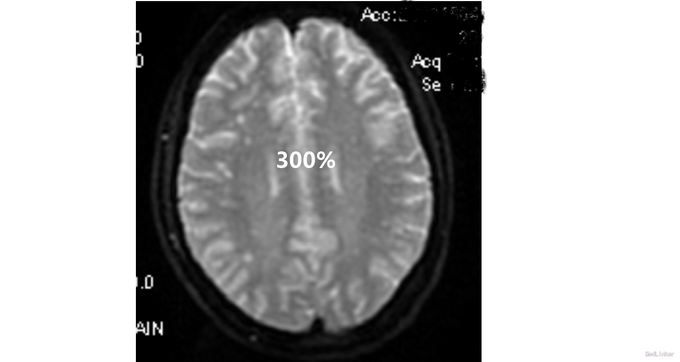

查体:生命体征平稳,心律齐,未闻及病理性杂音,双肺呼吸音清,未闻及干湿罗音。腹软,无压痛及反跳痛,肝脾肋下未及,双下肢不肿。3月21日神经系统检查:意识清楚,回答问题有时不切题,记忆力下降,定向力可,存在幻听,双侧瞳孔等大等圆,光反射灵敏,双侧鼻唇沟对称,伸舌居中,四肢肌力、肌张力、腱反射正常,病理征未引出。颈软,Kernig征阴性,Brudzinski征阴性。3月26日神经系统检查:意识模糊,不能言语,查体不能配合,双侧瞳孔等大等圆,直径约3mm,双侧光反射均迟钝,眼球活动不配合,双侧鼻唇沟尚对称,伸舌不能配合,双上肢肌张力高,四肢肌力查体不配合,可见自主活动,肌力在3级以上。病理征阴性,左侧趾反射弱,疼痛刺激反应减弱,颈强2指,Kernig征双侧阳性,Brudzinski征阴性。 脑脊液检查示:3月26日脑脊液检查:Pro 0.3g/L WBC 48 *10^6抗酸、墨汁染色均为阴性。脑脊液抗NMDA抗体IgG阳性,血抗NMDA抗体IgG 阳性,颅脑MRI平扫+flair+DWI:双侧额颞顶叶皮层下多发异常信号。肿瘤标志物检测(—)。我院子宫肌附件B超提示:右侧卵巢囊肿。